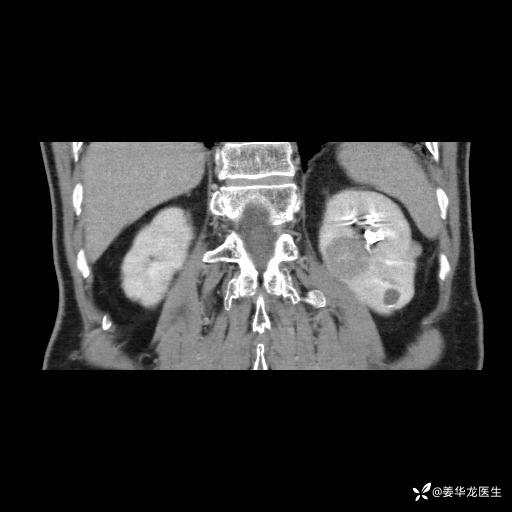

三、患者无任何基础病,为什么右肾GFR只有25ml/min,反尔有肿瘤的左肾GFR达38.8ml/min?

四、左肾根治疗切除术后,透析的机率有多大?

五、有没有必要复查肾动态显像?